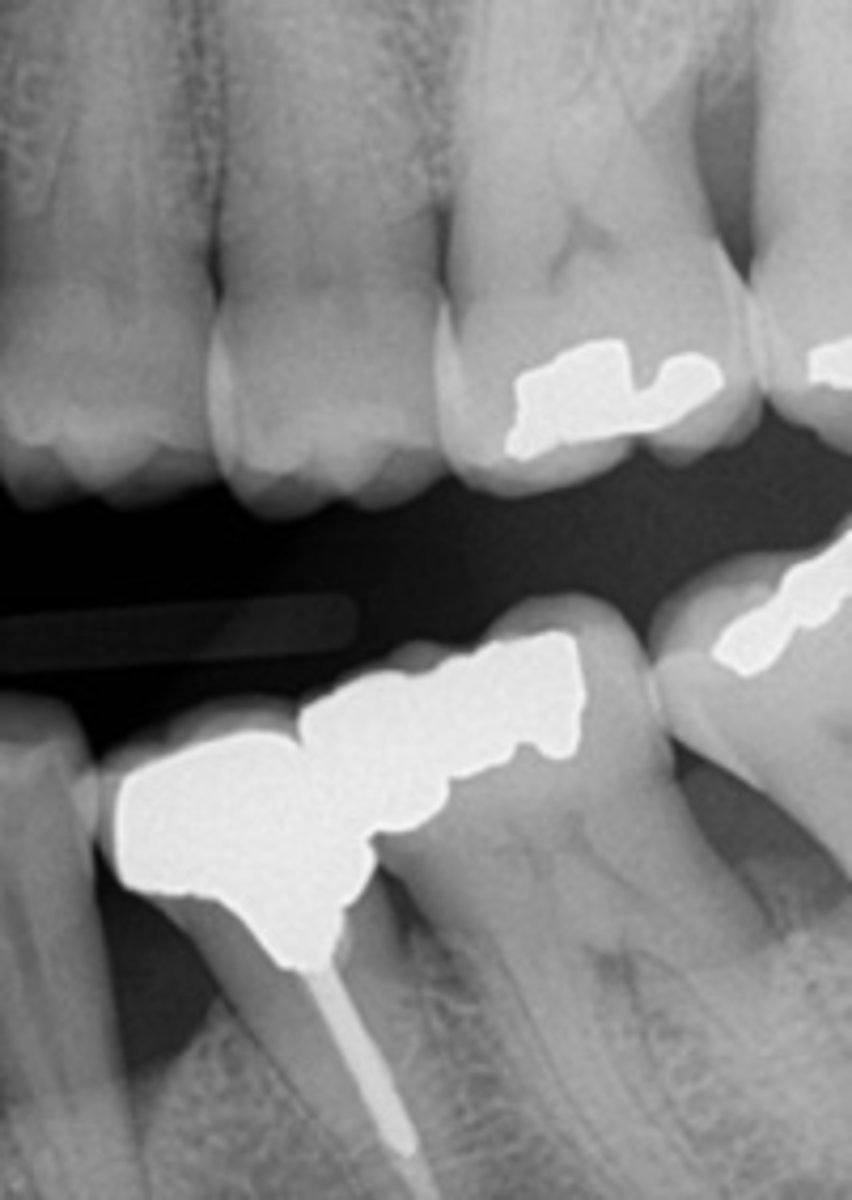

Vertical Bite-Wings

Used to examine the level of alveolar bone

-Placed with the long portion of the receptor in a vertical direction

-Often used as post-treatment or follow-up films for patients with bone loss caused by periodontal disease